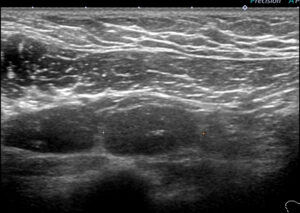

レベル2リンパ節 これが一番大きい 2㎝

形はリンパ節の形をしており「節外」では(画像上)なさそう。

大きなレベルⅡは、レベルⅢに近い部位までせり出し、その奥(図中央)にはレベルⅢが

確認できる。